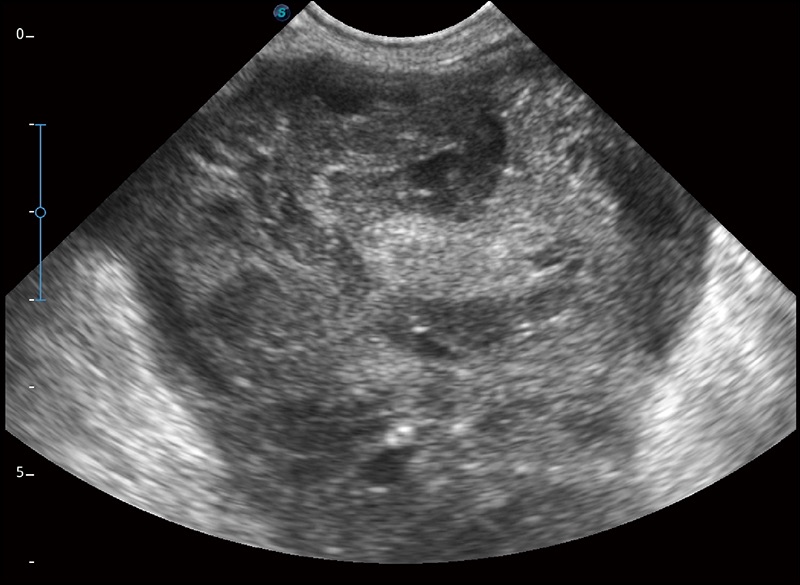

α1卓越的图像质量和便捷的工作流程,使每位宠物医生都能轻松扫查。其全面的兽用应用功能和紧凑型的结构设计,可以满足动物检查的多种需要。专业的预设检查模式和多领域测量软件包有助于为不同类型的动物提供检查, 让宠物医生能够出色的完成工作。

任意波束合成技术

在不牺牲时间分辨率的情况下提供出色的图像

空间复合成像

优化不同角度的图像